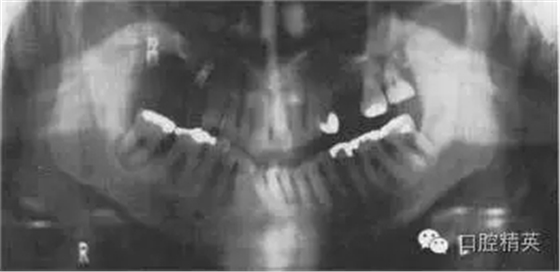

圖38.2 患者牙齒的全口牙位曲面體層X線片

牙齒全口牙位曲面體層X線片如圖38.2所示,你看到了什么?

答:全口牙位曲面體層X線片不是很清晰?;颊哳^位沒擺正,使圖像產(chǎn)生很大扭曲。下頜骨下緣呈彎曲圖像,且下前牙被縮短了。因?yàn)轶w位不正,脊柱陰影也被增強(qiáng)了。因?yàn)橛跋裰丿B,中線處的牙齒沒在中點(diǎn)。頭偏向一邊,一側(cè)影像被放大。這在后牙牙冠上很容易看出來,因?yàn)橛覀?cè)比左側(cè)的牙冠大?;颊叩男g(shù)后片如圖38.3,它顯示了正常片子應(yīng)顯示的樣子。